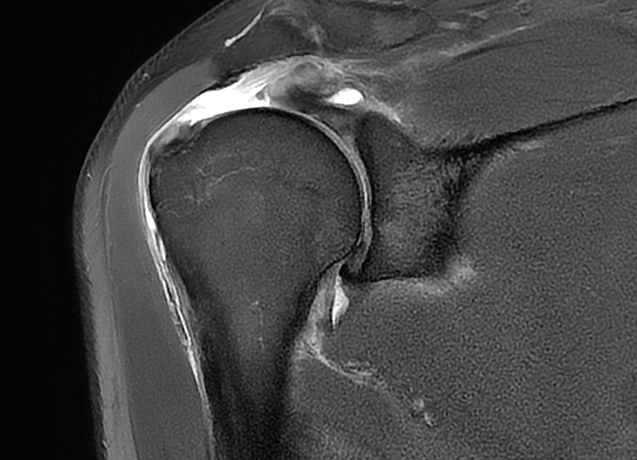

회전근개 전층이 찢어진 완전파열의 경우 수술적 치료가 원칙입니다.

비수술 치료를 일정기간 시행해도 증상이 호전되지 않거나, 파열 크기가 큰 경우,

젊고 활동적인 환자, 어깨 통증으로 일상생활에 심각한 지장이 있는 경우 등에는

수술적 치료가 권장됩니다.

회전근개 봉합술이란?

회전근개 봉합술은 어깨관절에서 파열된 회전근개 힘줄을

원래 위치에 다시 부착하는 수술입니다.

파열된 힘줄을 봉합나사 등을 이용해 뼈에 단단히 고정시켜

어깨관절의 기능을 회복시킵니다.

대부분 최소침습 관절내시경 수술로 진행됩니다.